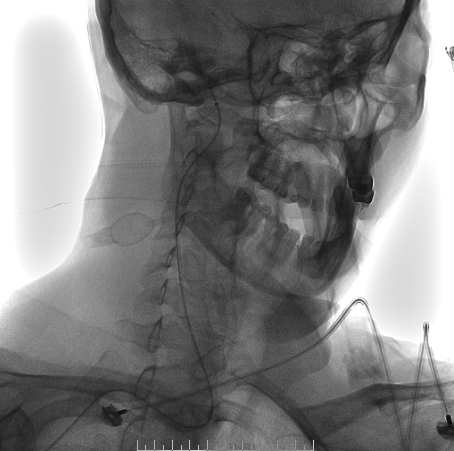

脑血管造影

左侧椎动脉造影

左侧颈总造影

右侧颈总造影:右侧大脑中动脉瘤